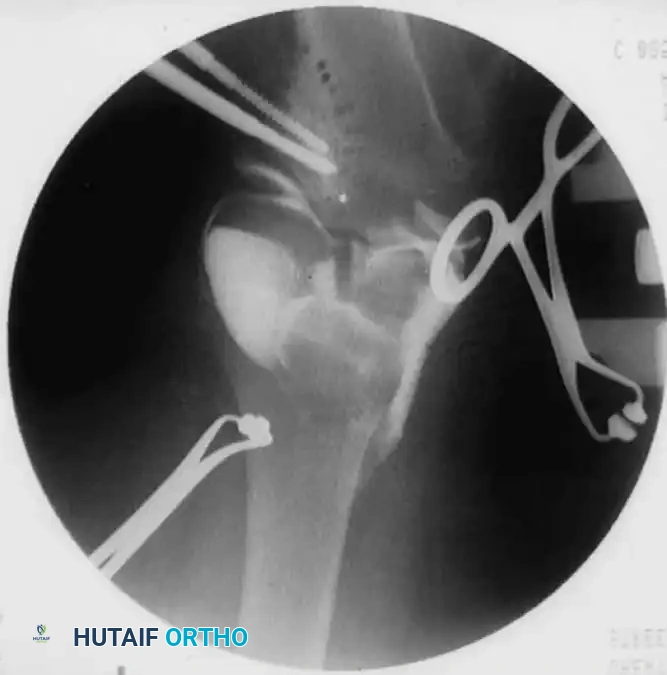

- Osteotomy Execution: Guide pins are placed under fluoroscopic guidance to define the osteotomy plane. The cut is made distal to the tibial tubercle to ensure the extensor mechanism remains attached to the proximal fragment.

- Deformity Correction: The distal fragment is translated laterally, angulated into valgus, and externally rotated to correct the multiplanar deformity.

- Fixation: Fixation depends on surgeon preference and patient age. Options include crossed Kirschner wires incorporated into a long-leg cast, rigid internal fixation (plates and screws), or external fixation (Ilizarov or Taylor Spatial Frame), which allows for gradual postoperative correction.

1. Intraepiphyseal Osteotomy: To elevate the depressed medial tibial plateau and reconstruct the horizontal joint line.

2. Metaphyseal Valgus Osteotomy: To correct the diaphyseal varus angulation.

Schoenecker et al. reported successful elevation of the medial tibial plateau in patients aged 10 to 13 years with average preoperative varus deformities of 25 degrees. The procedure involves an osteotomy through the epiphysis, elevating the medial plateau to match the lateral plateau, and supporting the elevation with structural bone graft.

Surgical Warning: Intraepiphyseal osteotomies carry a high risk of intra-articular fracture, avascular necrosis of the elevated fragment, and permanent physeal arrest. Meticulous fluoroscopic guidance and rigid fixation are absolute requirements.